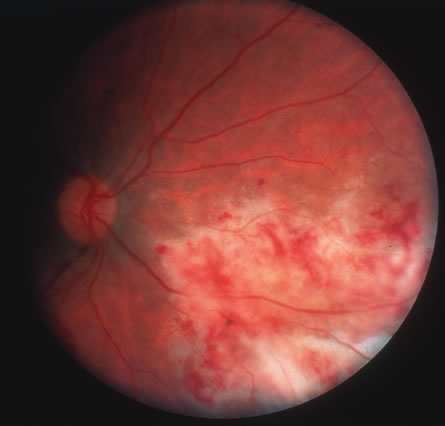

CMV retinitis is common in patients with AIDS. Perivascular granular white or yellowish infiltrates with hemorrhage are typical (Fig. 7). Minimal vitritis or anterior uveitis may be present. The posterior pole, including optic nerve, or peripheral retina may be involved. Optic neuritis may be retrobulbar. Resolution of retinal lesions reveals local retinal atrophy and pigment dispersion. Iridocyclitis may occur secondary to infection of ciliary processes. CMV retinitis in patients with AIDS is considered a poor prognostic sign in terms of life expectancy. Congenital CMV infection may also cause retinitis, as well as anterior uveitis, cataract, and optic atrophy. New foci of retinochoroiditis can develop in later years of congenital infection, and such infants require periodic reexamination as long as virus is shed in the urine.